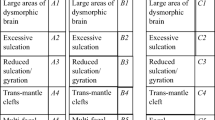

The expert panel categorised the type of abnormality present using a flow diagram devised by two of the authors (A.R. and P.D.G.) (Fig. 1). Primary classification produced three groups based on laterality of CFA; group A—bilateral, asymmetric CFA; group B—bilateral, symmetric CFA; and group C—unilateral CFA. Seventeen categories (five from group A, six from group B and six from group C) were then defined from fine anatomical features as shown in Figs. 2, 3 and 4: group A, bilateral asymmetric—A1, large areas of dysmorphic brain; A2, excessive sulcation/gyration; A3, shallow opercula; A4, trans-mantle clefts; A5, multi-focal ‘bites’. Group B, bilateral symmetric: B1, large areas of dysmorphic brain; B2, excessive sulcation/gyration; B3, reduced sulcation/gyration; B4, trans-mantle cleft; B5, multi-focal ‘bites’; B6, cobblestone cortex. Group C, unilateral: C1, large area of dysmorphic brain; C2, excessive sulcation/gyration; C3, poor sulcation/gyration; C4, trans-mantle cleft; C5, focal distortion; C6, enlarged hemisphere. In cases where more than one feature was present, the panel was asked to define the most prominent anatomical abnormality and provide a free-text description of the other features. The reviewers specified the location of the abnormality in cases of abnormal sulcation (A2, A3, B2, B3, C2 and C3). The head size and sex distribution of the complete cohort, groups and categories was assessed using 95% confidence intervals.

Examples of group A—bilateral asymmetric CFA as defined in this paper. Dysmorphic condition was defined as the clear abnormal distortion of profile of one or more lobes on both cortical and ventricular surface side, when present as dominant finding. Excessive gyration/sulcation was defined as the number of gyri/sulci of one or more lobes was higher than expected for gestational age, when present as dominant finding. Definitions of the other categories are self-explanatory. A1 (a)—axial and coronal images of a foetus (33 gestational weeks) with bilateral, asymmetric areas of dysmorphic brain (arrows). Other features recognised in this case were hypoplasia of the brainstem and cerebellum (not shown). A2 (b)—axial and coronal images of a foetus (23 gestational weeks) with bilateral asymmetric excessive sulcation/gyration (arrows). Cerebellar hypoplasia was also present. A3 (c)—axial and coronal images of a foetus (23 gestational weeks) with bilateral asymmetric shallow operculi (arrows). The foetus had severe hypogenesis of corpus callosum and unilateral mild ventriculomegaly. A4 (d)—axial and coronal images of a foetus (33 gestational weeks) with bilateral asymmetric trans-mantle clefts (arrows). The foetus had ventriculomegaly and was microcephalic. A5 (e)—coronal and sagittal images of a foetus (25 gestational weeks) with bilateral asymmetric multi-focal “bites” (arrows)

Examples of group B—bilateral symmetric CFA as defined in this paper. B1 (a)—axial and coronal images of a foetus (21 gestational weeks) with bilateral, symmetric areas of dysmorphic brain (arrows). Agenesis of the corpus callosum was also present. B2 (b)—axial and coronal images of a foetus (21 gestational weeks) with bilateral, symmetric excessive sulcation/gyration (arrows). B3 (c)—axial and coronal images of a foetus (30 gestational weeks) with bilateral, symmetric reduced sulcation/gyration (arrows). The foetus was microcephalic. B4 (d)—axial and coronal images of a foetus (27 gestational weeks) with bilateral, symmetric trans-mantle cleft (arrows). B5—there were no cases of bilateral symmetric multi-focal “bites” in the cohort. B6 (e)—axial and coronal images of a foetus (31 gestational weeks) with bilateral symmetric cobblestone cortex (arrows). Microphthalmia, abnormal brainstem (not shown) and ventriculomegaly were also present

Examples of group C—unilateral CFA as defined in this paper. C1 (a)—axial images of a foetus (25 gestational weeks) with a unilateral area of dysmorphic brain (arrows). There is abnormal low T2-weighted signal in the affected (left) hemisphere. The foetus also had agenesis of the corpus callosum and interhemispheric cyst. C2 (b)—axial and coronal images of a foetus (32 gestational weeks) with unilateral excessive sulcation/gyration (numerous, small gyri) in part of the left hemisphere (arrows). C3 (c)—axial and coronal images of a foetus (35 gestational weeks) with unilateral poor sulcation/gyration of the left hemisphere (arrows), that is hypoplastic. Unevenly diffuse reduced signal within white matter is present. The foetus also had a Dandy-Walker malformation (not shown). C4 (d)—axial and coronal images of a foetus (21 gestational weeks) with unilateral trans-mantle cleft in the left hemisphere (arrows). The cavum of septum pellucidum is absent. C5 (e)—axial and coronal images of a foetus (18 gestational weeks) with unilateral focal distortion in the form of an early abnormal sulcus in the left hemisphere (arrows). This foetus also had hypoplasia of the corpus callosum. C6 (f)—axial and coronal images of a foetus (26 gestational weeks) with unilateral enlarged right hemisphere (arrows), which is also generally malformed